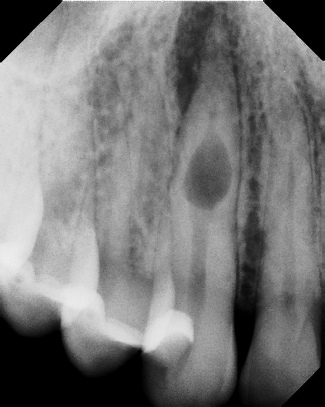

COMPLICATED ANATOMY LARGE LESIONS CALCIFIED CANALS PERFORATION / RESORPTION SEPARATED INSTRUMENTS SURGICAL CASES RETREATMENT / pOST REMOVAL OPEN APICES ACCESS THRU CROWNS Root Canal Case Portfolio